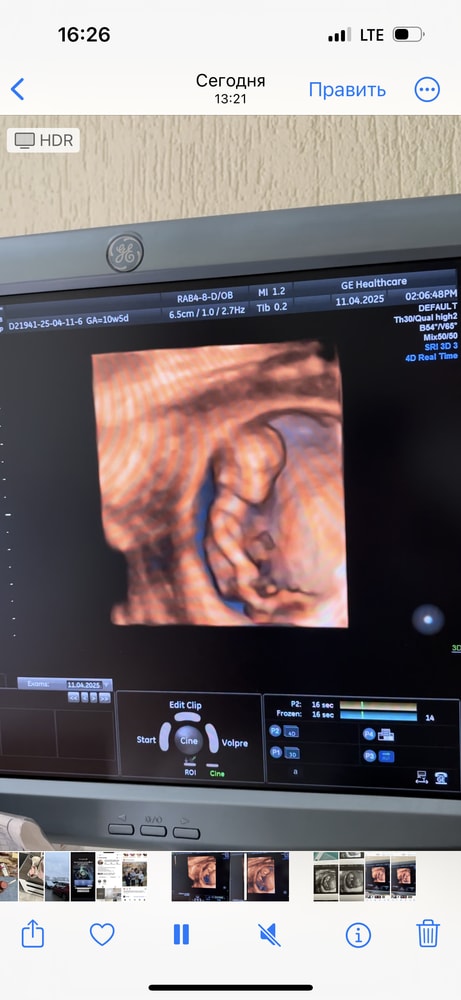

Вот 10 недельИзображение

Изображение 10 недель ровно, инопланетянин))))